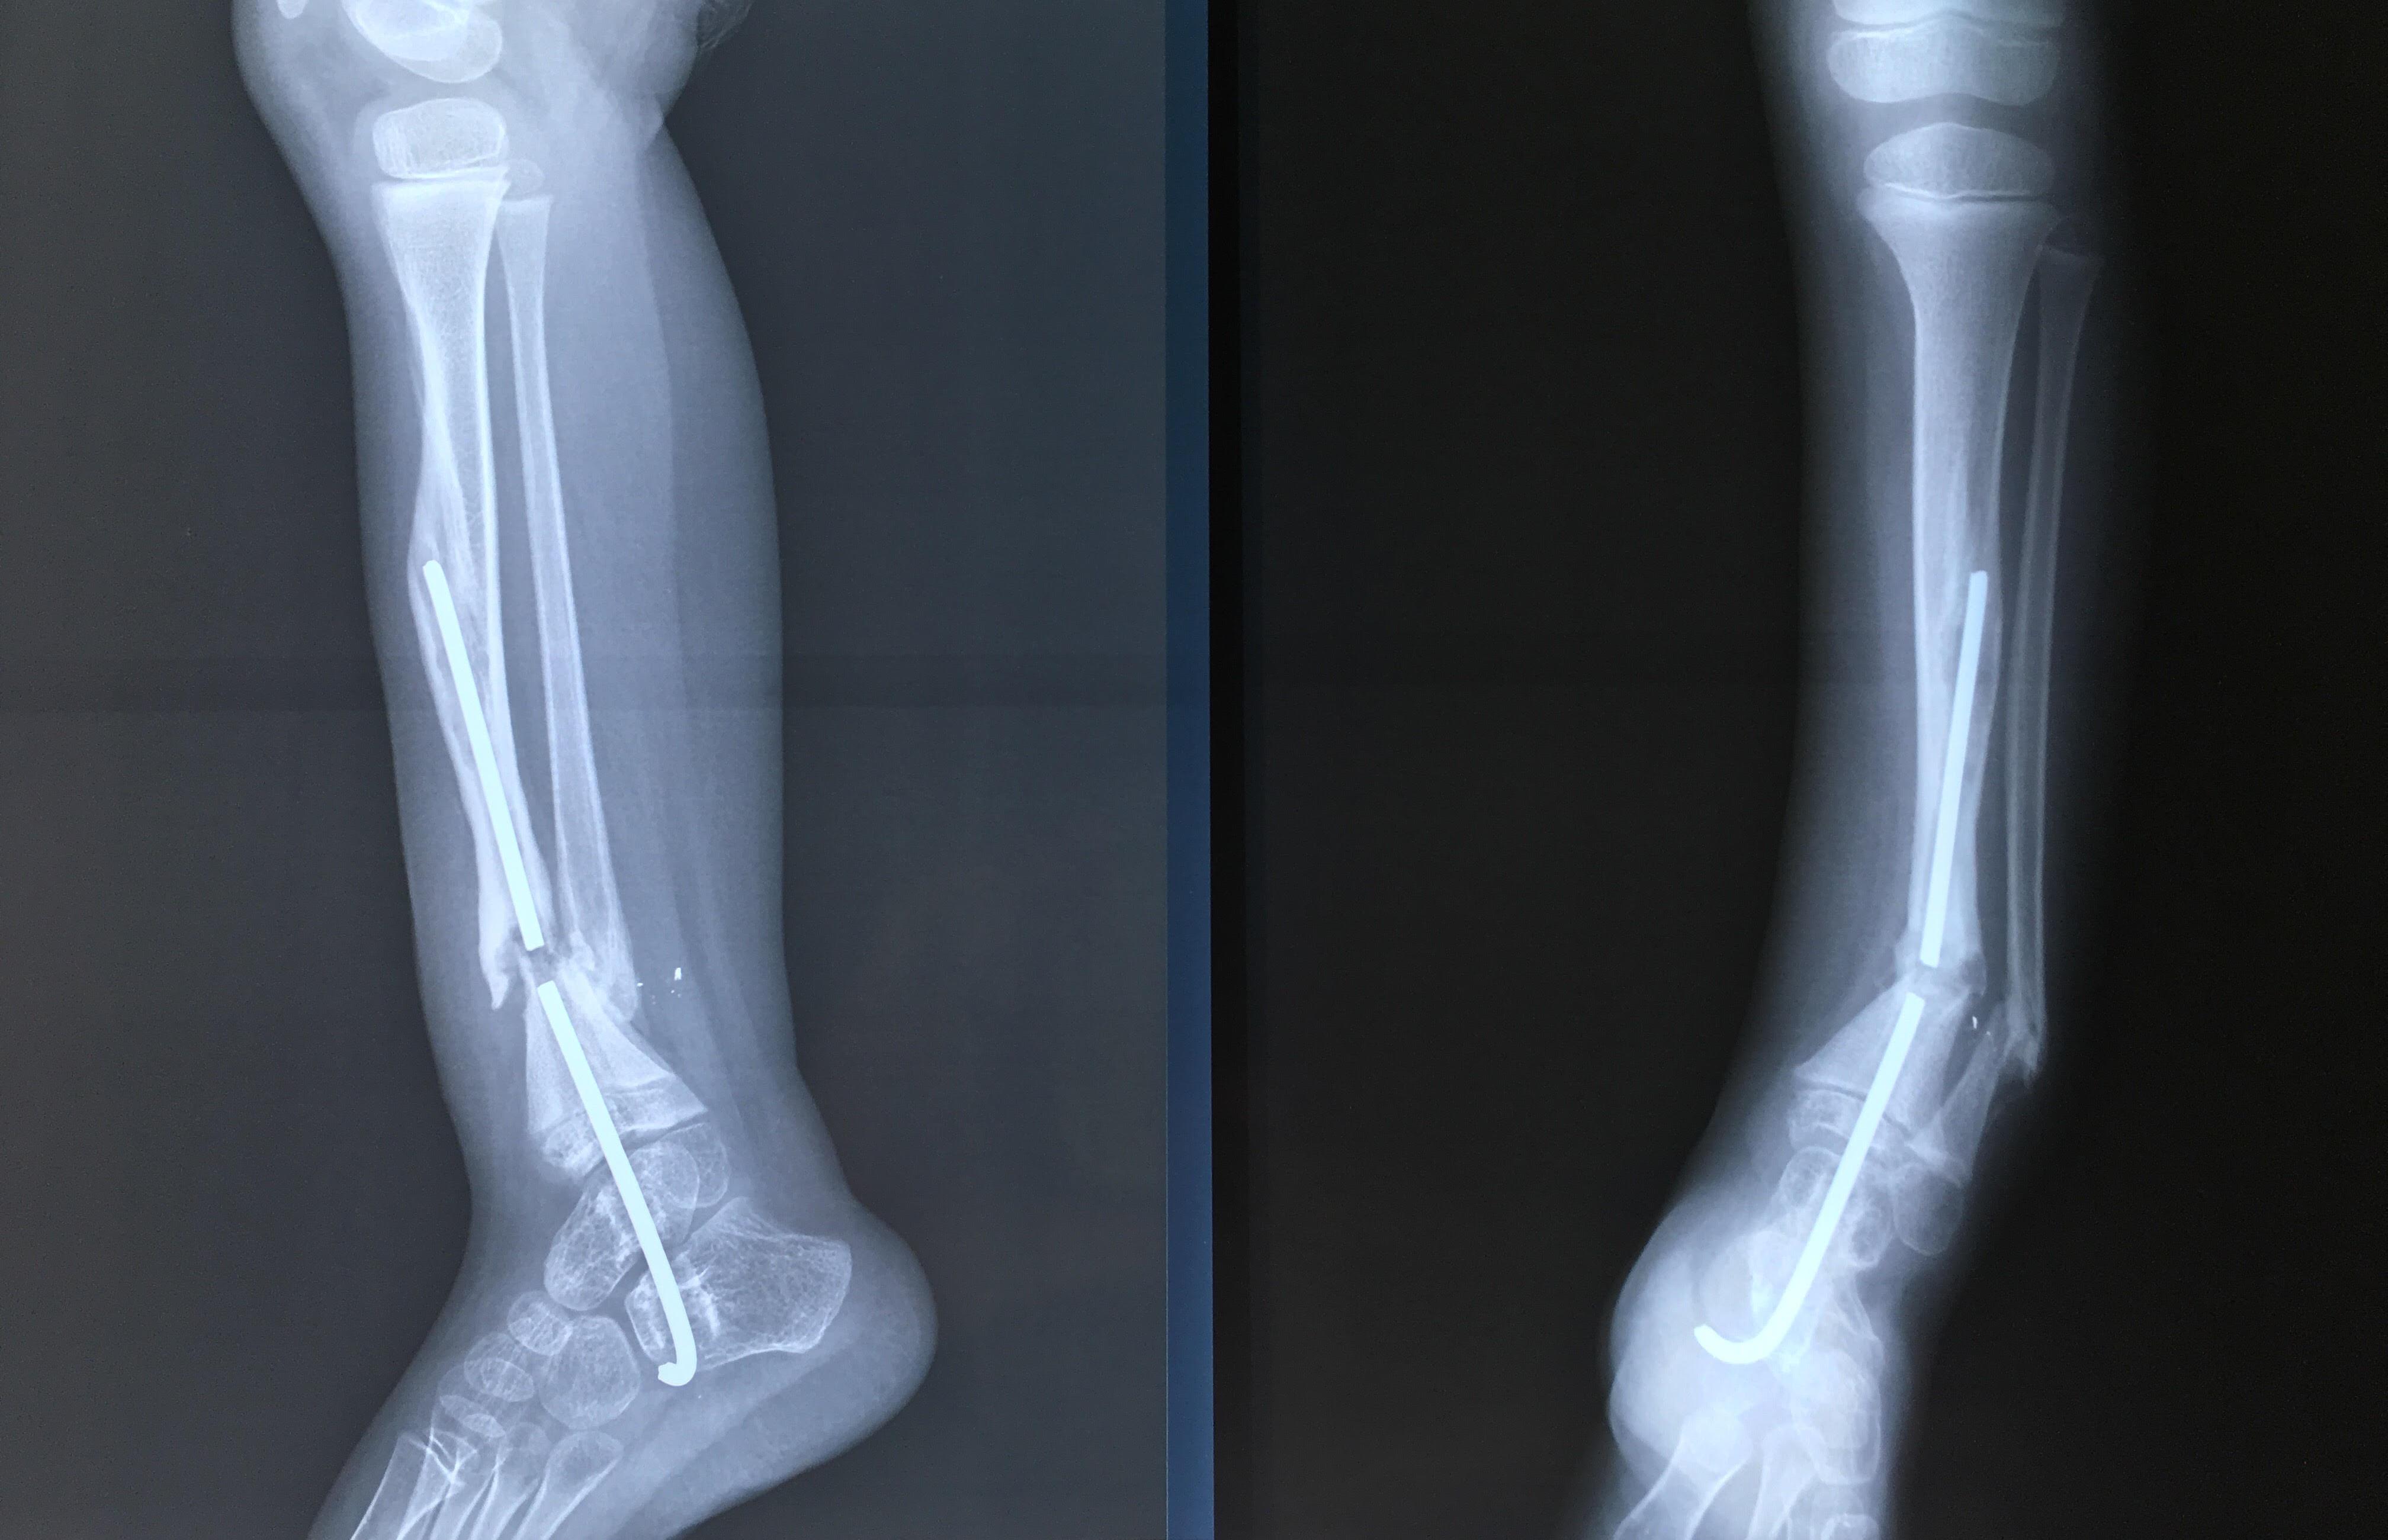

Phẫu thuật thành công ca bệnh hiếm gặp...khớp giả bẩm sinh xương chày

26/06/2019 17:00

Đã xem: 3526

Bệnh viện Chấn thương- Chỉnh hình Nghệ An, vừa phẫu thuật thành công cho bệnh nhi khớp giả bẩm sinh xương chày